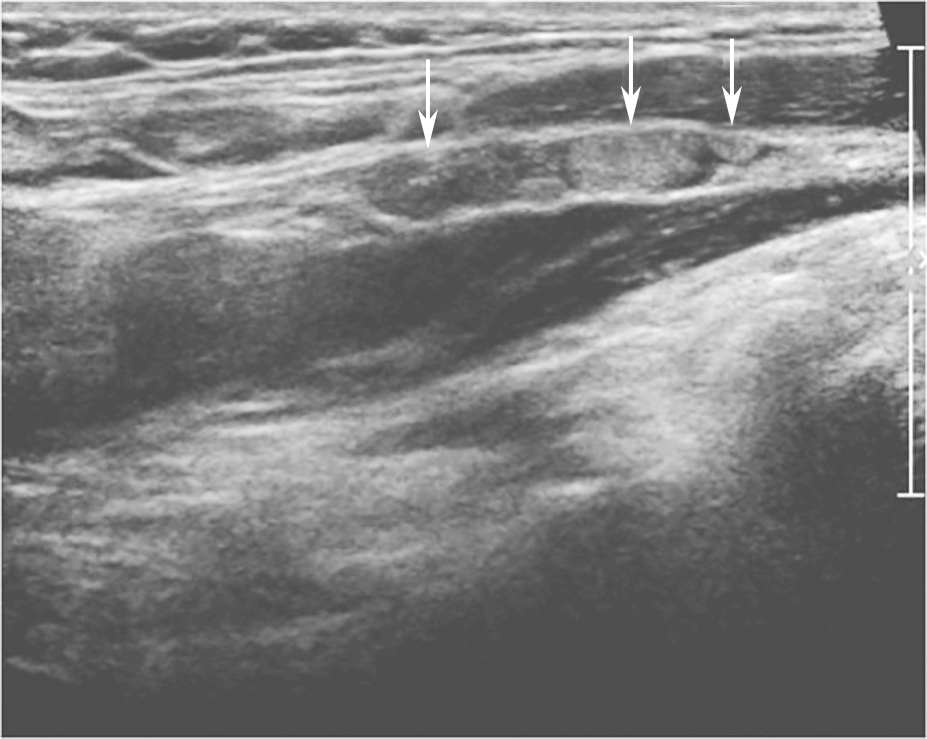

图11右侧颈部纵切面:甲状腺右叶中部中等回声(箭头所示):内部回声不均伴厚薄不一低回声晕

:内部回声不均伴厚薄不一低回声晕.jpg)